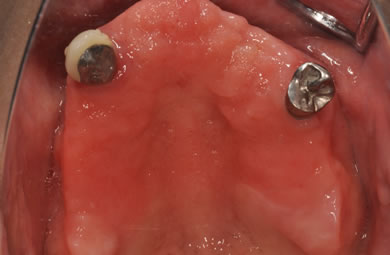

骨再生スピードインプラント治療+AGC連結セラミック治療

| 性別/年齢 | 女性 / 57歳 | ||||||||||||||||||||||||||||||||

| 主訴 | 全体的に歯が無いので相談したい。 | ||||||||||||||||||||||||||||||||

| 治療方針 | 骨再生療法にて骨量を回復するとともに軟組織も移植し、機能的回復だけでなく審美的回復も行う。 | ||||||||||||||||||||||||||||||||

| 治療内容 | インプラント12本(サイナスリフト+GBR+抜歯即日スピードインプラント+遊離歯肉移植)、AGCハイブリッドセラミック連結ブリッジ2装置(上顎・下顎)、テンポラリーインプラント2本 | ||||||||||||||||||||||||||||||||

| 総治療費 | 6,019,650円 | ||||||||||||||||||||||||||||||||

| 治療期間 | 1年0ヶ月 |